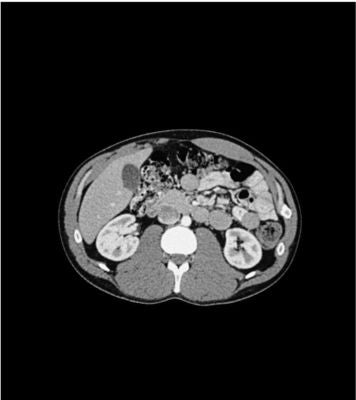

Description

This phantom simulates a contrast medium-enhanced abdomen in the portal venous phase. It covers the eleventh thoracic vertebra to the fourth lumbar vertebra (partially included). The phantom can be used in CT (including CBCT) to evaluate and optimize imaging performance and post-processing applications, including AI-enabled applications. It is also suited for training purposes. The phantom provides a detailed and realistic simulation of soft and bone tissue. Air voids are filled with a cellulose-polymer composite of approx. -160 HU.